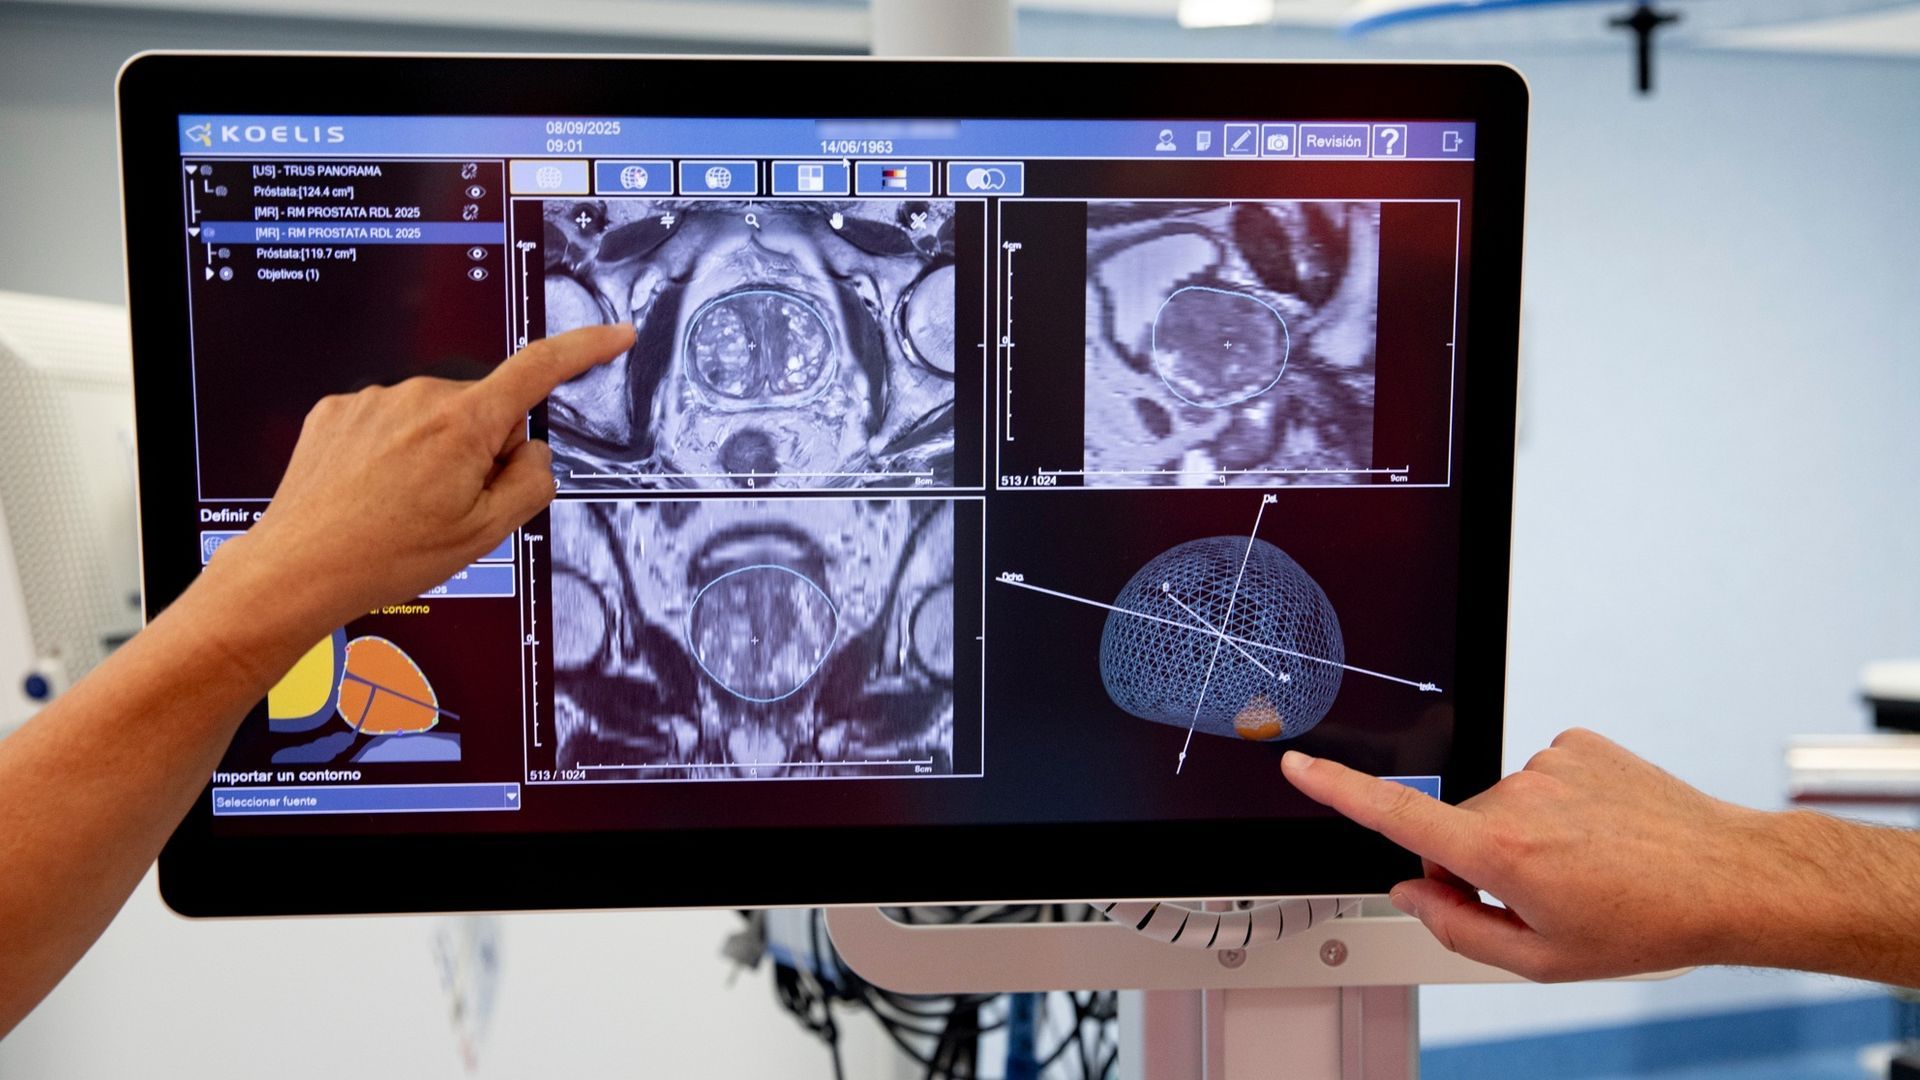

Dos pacientes del Hospital Virgen del Rocío, dependiente del Servicio Andaluz de Salud (SAS) de la Junta...